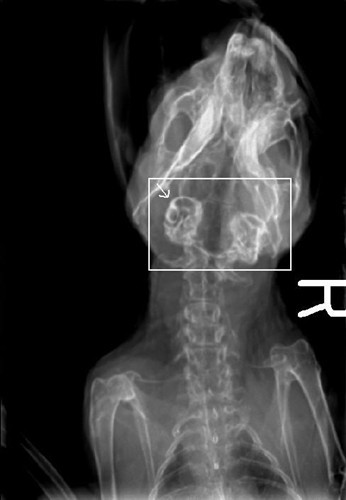

Sooo Dave actually uploaded them(xrays) for me!!! YEAH!!

And a top down (Mikey is ‘photobombing” this)

Now for the xrays (Though I probably didn’t need to say that-you could probably guess by looking at them

Well their are two main causes but there are other causes like stroke, tumor abscess-so they eliminated that; AND the ‘bulba’ (sp??) are thickened which may be incidental but may be something so they were good to do-I’d like-eventually to do xrays on everyone but at this point only when necessary.

The dark parts in the centre are his ‘bulba’ they are basically round thing at the base of the ear canal. They are thickend which is why they are showing up so much-this could be nothing , why he’s deaf, or someting we need to treat after the tilt is treated. They shold be nice light circels like his eyes (you can sort of see his eye sockets in one of the pics) -I thnk thats what you were asking about.

Hehe OK the first xray you posted is a top down-so where the R is-is his right hand side, and left is left of the picture.

The second one-that’s a hard one

He’s partially upside down in that one. In the top right you can see his arms. the face is pretty blurry and his ears are dangling bottom left ![]()